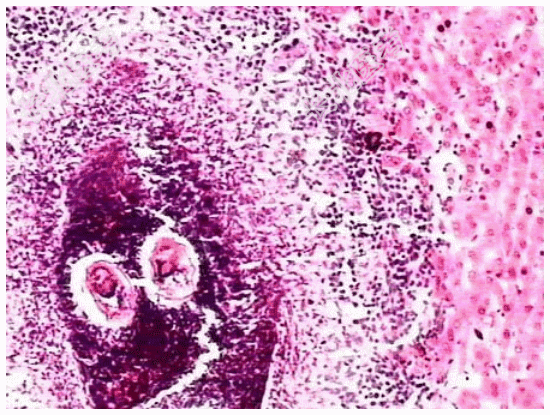

- [材料题] 患者,男,50岁,湖南岳阳人。因贫血、白细胞、血小板减少并腹水入院,临床诊断为“肝硬化”。肝穿刺活检镜下观如图所示,临床拟诊血吸虫性肝硬化。

- 简答题1、血吸虫病的病因包括?

- 简答题2、该疾病病理学改变表现为?